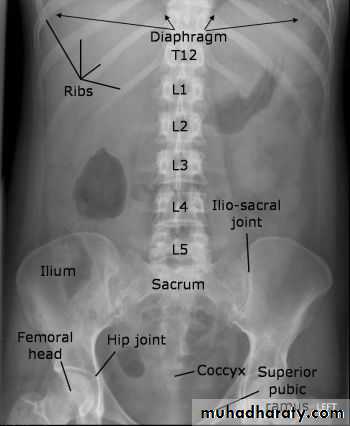

How to look at a plain abdominal film :

• Analyze the intestinal gas pattern and identify any dilated portion of the gastrointestinal tract

• Look for gas outside the lumen of the bowel

• Look for ascites and soft tissue masses in the abdomen and pelvis

• If there are any calcifications, try to locate exactly where they lie

• Assess the size of the liver and spleen